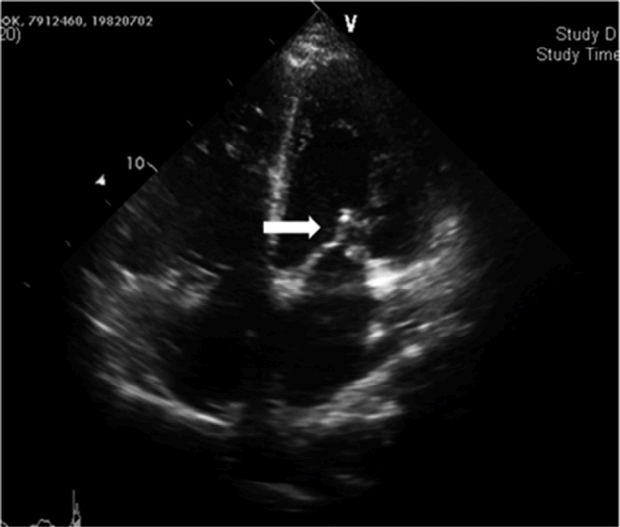

Figure 3.

Transesophageal echocardiogram reveals severe mitral regurgitation associated with multiple ruptured chordae.

32세 남자가 내원 당일부터 시작된 호흡곤란 및 발열을 주소로 응급실을 방문하였다. 8년 전 고혈압 및 만성 신부전을 진단받고 2년 전 말기 신부전으로 진행되어 타 병원에서 유지 혈액투석 중이었으며, 3개월 전 유사한 증상으로 폐렴 진단 하에 항생제 치료를 받았던 병력이 있었다.내원 당시 호흡곤란 및 발열 외에 기침, 가래 등의 동반 증상은 없었으며, 활력 징후는 혈압 131/89 mmHg, 심박동수 108회/분, 호흡수 30회/분, 체온 37.8℃였다. 청진상 양측 폐 영역에서 수포음이 들렸으나 빈맥으로 인하여 심잡음은 확인되지 않았다. Osler's node나 Roth spot 등은 관찰되지 않았다. 동맥혈 가스 분석에서 pH 7.434, 이산화탄소분압 34.3 mmHg, 산소분압 66.0 mmHg, 중탄산염 22.5 mmol/L, 산소포화도 92.7%였다. 말초혈액 검사 결과는 혈색소 7.2 g/dL, 적혈구 용적률 23.7%, 백혈구 12,970/mm3 (중성구 84.9%), 혈소판 274 × 103/mm3였고, 혈청 생화학 검사 결과는 혈중요소질소 34.7 mg/dL, 크레아티닌 10.46 mg/dL, 총 단백질 6.7 g/dL, 알부민 3.6 g/dL, 나트륨 136 mEq/L, 칼륨 4.4 mEq/L, 클로라이드 98 mEq/L, C 반응성단백질(CRP) 7.80 mg/L (정상 범위: < 0.3)로 측정되었다. C3, C4, rheumatoid factor, anti-dsDNA Ab 및 anti-GBM Ab는 모두 정상 범위 또는 음성 소견이었다. 흉부 엑스선 촬영에서는 양측 폐음영이 증가되어 있는 폐부종이 관찰되었고, 이전과 비교하여 심장비대 소견이 동반되어 있었다(Fig. 1A). 흉부 전산화단층촬영에서 양측 폐부종 및 심비대, 소량의 늑막액과 심낭액이 확인되었고, 폐렴 의심 소견은 보이지 않았다(Fig. 1B).내원 초기 유지 혈액투석을 받고 있는 투석 환자에서 체액 과다에 의한 심한 급성 폐부종으로 판단하여 응급 혈액투석을 시행하였다. 투석 후 흉부 엑스선에서 폐부종은 호전되었으나 심장비대 소견은 지속되었다. 추가로 확인한 심장 표지자 검사는 troponin I 양성, troponin T 0.520 ng/mL (정상범위: < 0.099), B-type natriuretic peptide (BNP) 27,863 pg/mL (정상 범위: 5-125)로 측정되었으며, 심전도에서 심박수 102회의 동성빈맥 및 V2-3에 이상 Q파가 관찰되어 심초음파를 시행하였다. 경흉부 심초음파에서 심박출률은 64%로 정상 범위에 있었으나 양심방의 비대와 함께 승모판에 1.07 × 0.45 cm 크기의 우종 및 중증 승모판 폐쇄부전이 발견되었다(Fig. 2). 이어서 시행한 경식도 심초음파 검사 결과 승모판 전엽의 외측에 2개 이상의 다발성건삭파열(chordae rupture)과 이로 인한 중증 승모판 폐쇄부전이 확인되었다(Fig. 3).환자의 신체 검진상 immunologic phenomena인 Osler's node나 Roth spot 등은 관찰되지 않았으나, 심초음파 검사상 감염성 심내막염이 의심되어 곧바로 혈액 배양 검사를 하고, 경험적 항생제로 vancomycin을 투여하고 흉부외과로 전과하여 응급으로 개흉술을 시행하였다. 수술시 심초음파에서 보였던 1 cm 가량의 우종을 확인하고 제거하였으며 승모판치환술을 시행하였다. 내원 당일 시행했던 혈액 배양 검사 최종 결과에서 vancomycin, teicoplanin에만 감수성을 보이는 그람 양성 간균(Enterococcus faecalis)이 배양되어 vancomycin 항생제를 계속 투여하였다. 수술 후 28일째 시행한 심초음파에서 심박출률이 51%로 이전보다 약간 감소하였으나 치환된 인공 승모판이 잘 기능하고 있는 것을 확인하였고, 항생제는 총 6주 사용하였으며 와파린 용량 조절하여 술 후 51일째 퇴원하였다. 퇴원 후 외래에서 특별한 증상 없이 경과 관찰 중에 있다.